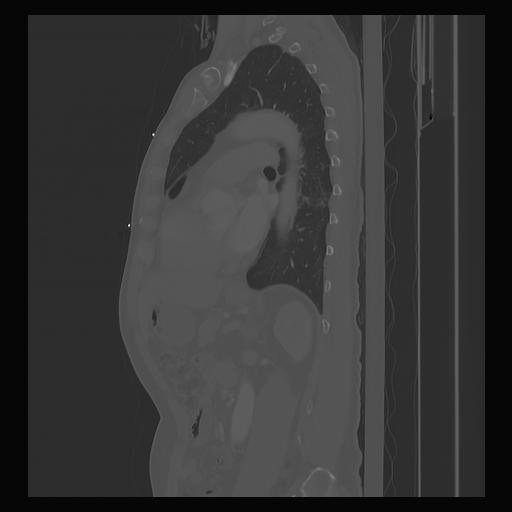

33 PULMON,CE,Sagittal,3.000,PULMON,Sagittal,